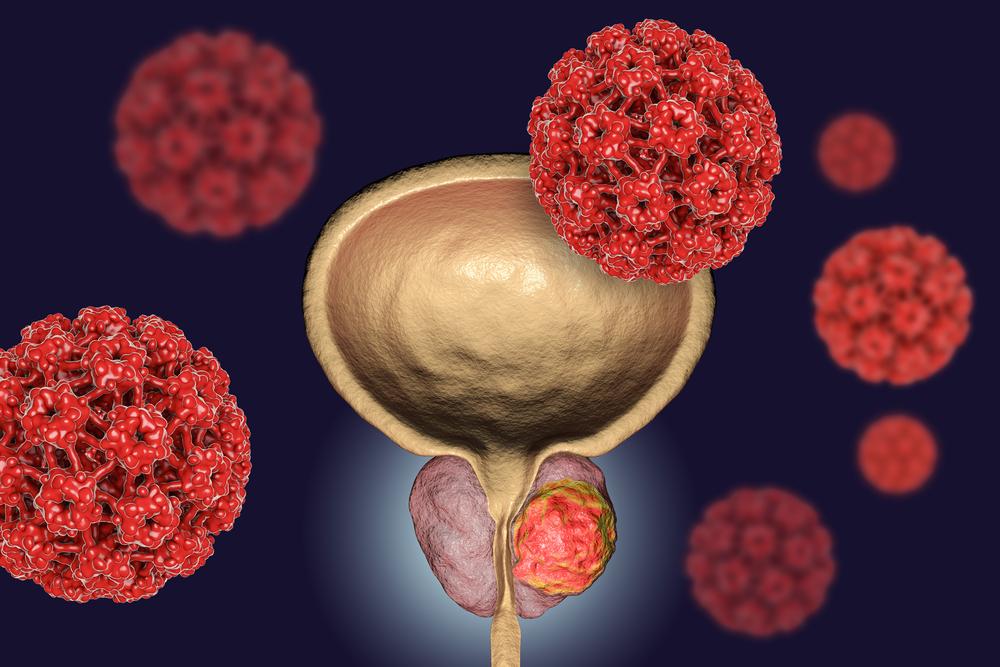

Prostate problems are common in men, especially with age. Conditions like benign prostatic hyperplasia (BPH), prostatitis, and prostate cancer can cause urinary difficulties, frequent urination, or pelvic discomfort. With early diagnosis and advanced treatment options, we offer personalized care to manage prostate health effectively and improve quality of life.